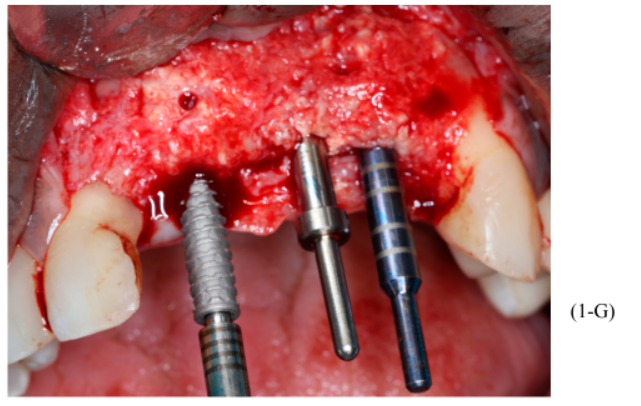

Figuras 3,4,5,6,7 e 8 – Sequência do primeiro ato cirúrgico, onde podemos observar (imagem 3) a incisão do tipo Newmann modificada para ampla visualização do campo operatório e as extrações dentárias. Podemos observar também a descorticalização do processo alveolar e a instalação dos parafusos tipo tenda Implacil De Bortoli de 10 mm, respeitando a distância de pelo menos 2 mm entre cabeças (imagem 4). Foram colocados dois gramas de biomaterial Bio-Oss Geistlich, preenchendo toda cavidade e alvéolos até a delimitação da cabeça dos parafusos (imagens 5 e 6). Antes do fechamento completo da ferida cirúrgica, colocamos membranas de PRF para auxílio na reparação tecidual e proteção do material de enxerto (imagem 7). Para fechamento da ferida cirúrgica, usamos fio do tipo Cytoplast, fornecido pela Implacil De Bortoli. É de extrema importância sua utilização, pois apresenta excelente elasticidade, acompanhando edema cirúrgico pós-operatório, o que diminui o risco de deiscência no pós-operatório.

Foram planejados três implantes do tipo Cone Morse Maestro Implacil De Bortoli 3.5 x 13 mm. Após remoção de maneira facilitada dos parafusos tenda, foram instalados três implantes em ótimo posicionamento tridimensional (imagens 1-E, 1-F, 1-G, 1-H). Todos apresentaram estabilidade primária de 35 Ncm de torque e aguardamos quatro meses para posterior reabilitação protética definitiva com próteses individualizadas de metalocerâmica do tipo parafusada.